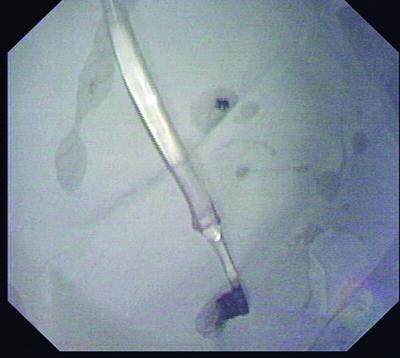

这支“调皮”的牙刷让姜女士吓得不轻。(医院供图)

食道

套取牙刷用的网篮

陈洁等医师最终确定的方案是:使用网篮(一种一头带有伸缩金属丝的套取工具),先套住牙刷柄的最末端,努力收紧往上提,到喉咙口时让姜女士头部尽量向后仰,顺着食道方向取出牙刷。

下午2点左右,医生开始“行动”了。然而实际操作远比想象的难得多。由于牙刷柄末端太滑,很难套;牙刷也太长,很难出喉咙口,但好在这个思路和方向没有问题,几个关键行动:套取刷柄、出喉咙口都先后得到解决。一个半小时的鏖战,这支“失足牙刷”终于被逮了出来。